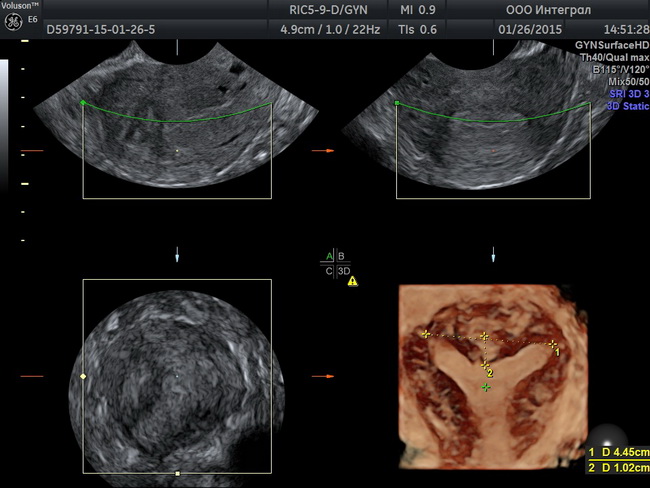

Университетская клиника «Я здорова!» проводит узи органов малого таза в Москве. Гинекологическое узи проходит безболезненно. После процедуры пациент получает подробный протокол с описанием диагностических данных. Ознакомиться с процедурой более подробно Вы можете на нашем сайте